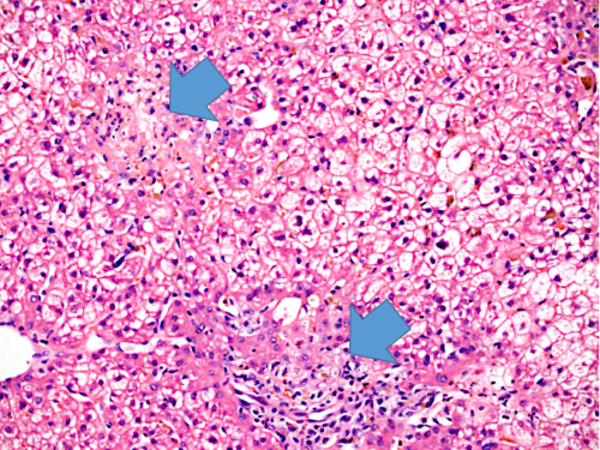

Recent cases